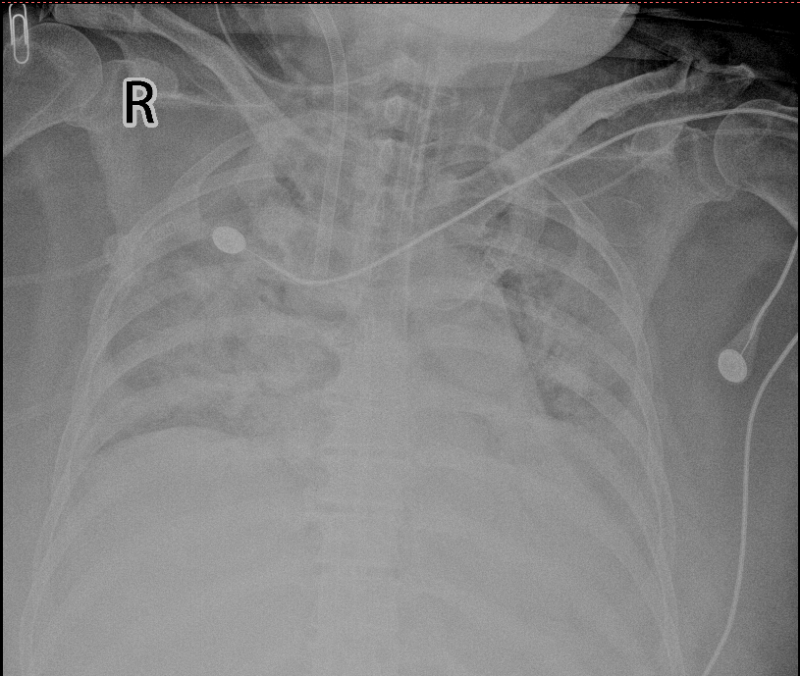

今年1月,赵阿姨因“感冒”症状到自治区南溪山医院呼吸与危重症医学科二病区就诊。经检测,她被确诊为甲型流感病毒感染。然而,病情迅速恶化,她的肺部出现严重感染,形成“大白肺”,导致急性呼吸衰竭,血氧饱和度骤降至66%,氧合指数仅为39mmHg,生命危在旦夕。

患者胸片“大白肺”

面对如此凶险的病情,呼吸与危重症医学科二病区主任屈东明立即联系综合重症医学科主任韦妍飞进行会诊。经评估,赵阿姨被诊断为:急性呼吸窘迫综合征(重度)、重症肺炎、甲型流感病毒感染(重症)、I型呼吸衰竭。此时,常规呼吸机治疗已无法维持她的生命,必须采取更积极的救治手段。